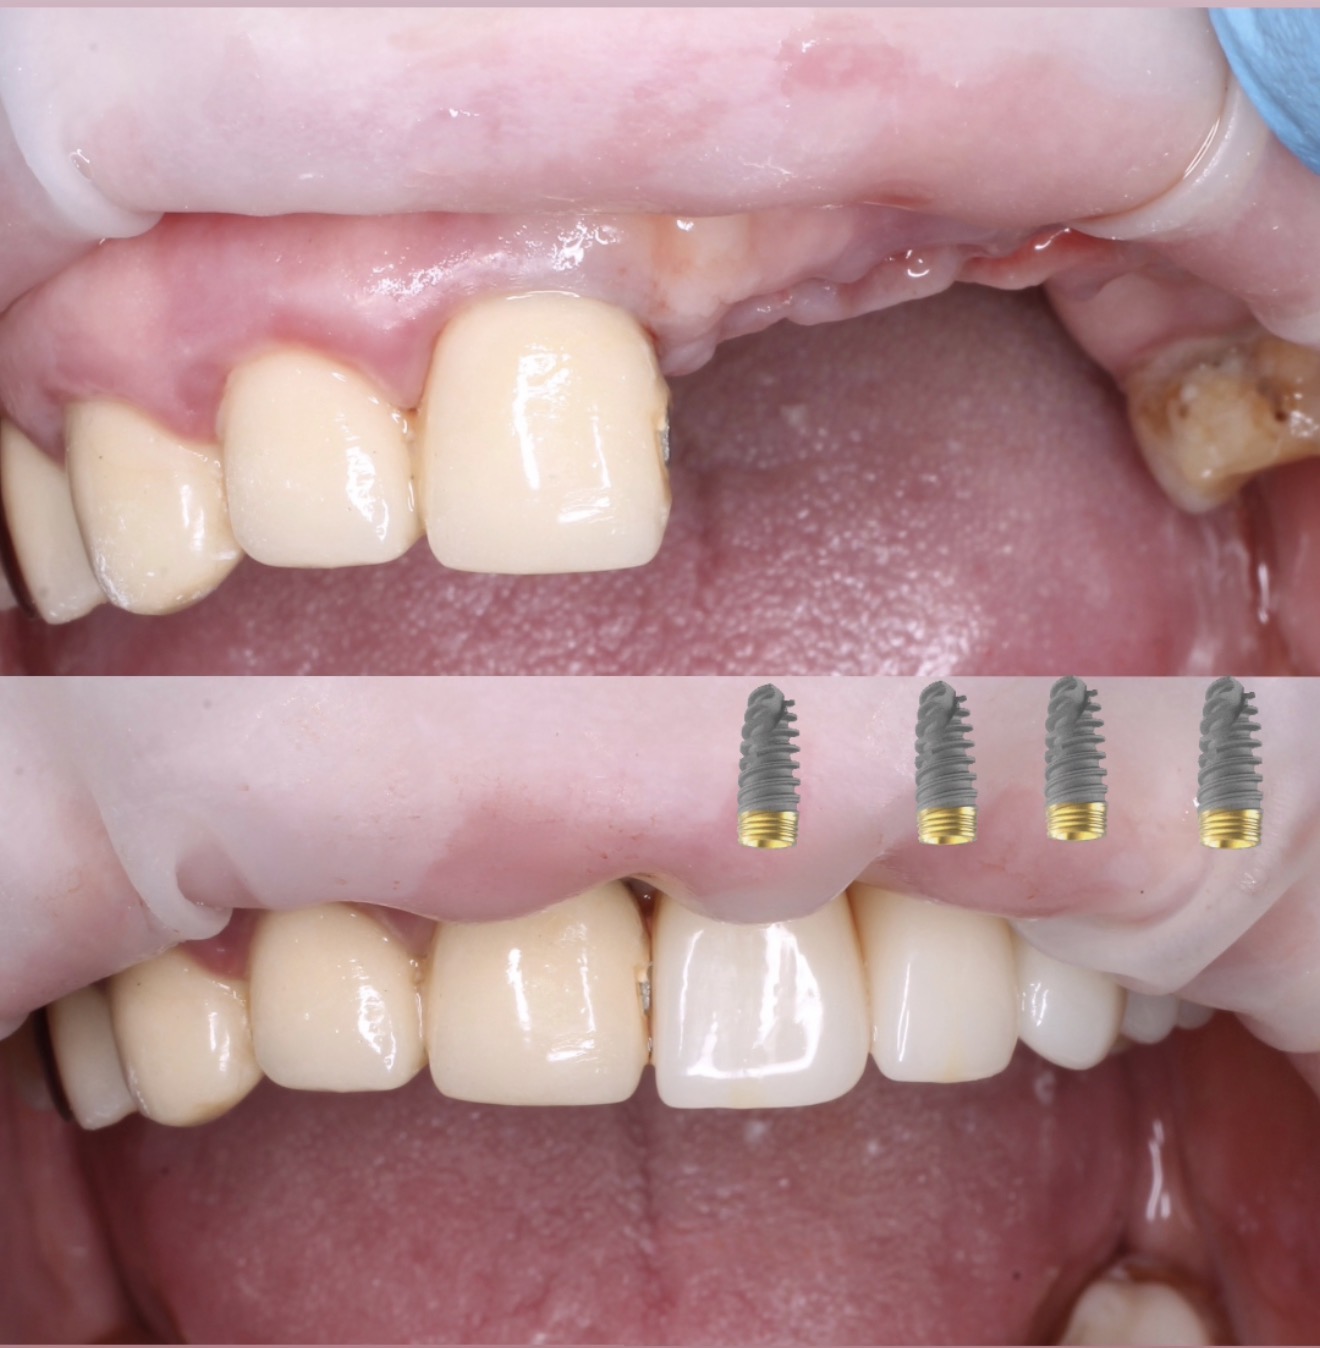

Имплантация зубов с хирургическим шаблоном